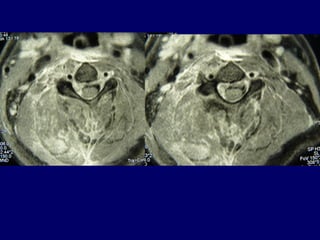

33rdrd

casecase

Ma. Pal.

F 56

Unknown origin

Symptoms

Neurologic deficit

Pain

Low fever

56

Follow upFollow up

Pus culture

(staphylococous aureous)

Antibiotics

i-v for 2 mts

orally for 6 mts

Complete neurologic recovery